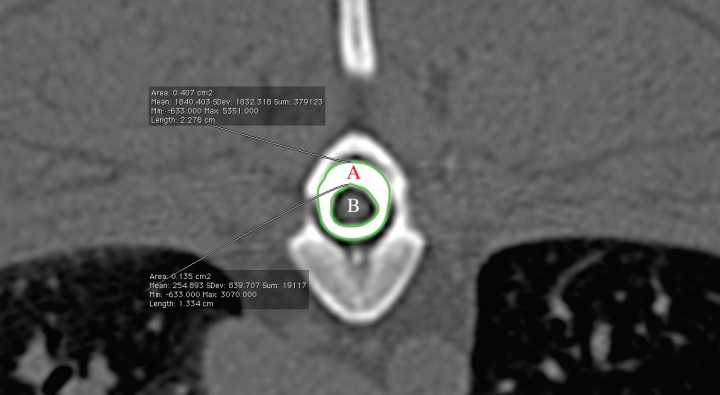

Para la determinación del grado de compresión medular que ejerce la cavitación leptomeníngea se utilizó el programa Osirix V.4.1.2 32 bit, utilizando reconstrucciones transversas de 0,5 mm en algoritmo hueso en el punto de máxima compresión medular, y estableciéndose el área del espacio subaracnoideo y de la médula espinal con el fin de calcular el grado de compresión relativa.

En la totalidad de los casos, los hallazgos radiológicos mostraron una dilatación dorsal o dorsolateral de la columna de contraste subaracnoidea, con desplazamiento y compresión del parénquima medular (Fig. 1). Los casos 1, 3, 5, 6, 8, 10 y 11, presentaron la forma típica de gota. En los restantes se observó una dilatación longitudinal del espacio subaracnoideo focal sin finalización abrupta, o en forma circunferencial. En el mielo-TAC, la extensión de la dilatación era variable, comprendiendo entre uno y cuatro cuerpos vertebrales y con un grado de compresión relativo de un 61’53% a un 99’82% (Fig. 2). En la Tabla 2 se muestra el grado de compresión medular relativo de la cavitación y su relación con la severidad de los signos clínicos.

<p>Mielo-TAC en corte transverso, con algoritmo hueso del caso 9 para la determinación del grado de compresión medular relativa en el punto de máxima compresión. A. Área del espacio subaracnoideo. B. Área medular.</p>

Mielo-TAC en corte transverso, con algoritmo hueso del caso 9 para la determinación del grado de compresión medular relativa en el punto de máxima compresión. A. Área del espacio subaracnoideo. B. Área medular.